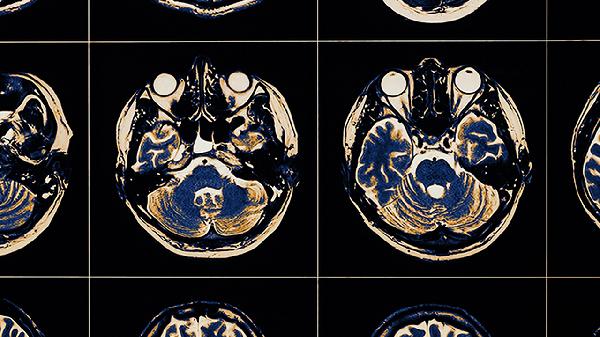

大脑通过约860亿神经元构成的复杂网络实现逻辑思维。突触可塑性允许神经连接根据经验调整,前额叶皮层负责工作记忆和规则提取,而胼胝体则协调左右脑的符号与空间信息处理。这种生物电化学系统通过神经递质传递信号,形成基础思维载体。

信息处理遵循从感觉登记到模式识别的层级模型。初级皮层处理原始数据,联合皮层进行特征整合,海马体参与记忆编码。大脑会优先处理威胁相关刺激,同时通过注意力过滤器筛选有效信息,这种自动化与受控处理的交替构成逻辑推理的基础框架。

思维依赖命题网络和心智模型两种表征系统。左脑颞叶处理语言逻辑关系,右脑顶叶构建空间关系图谱。当面对新问题时,大脑会激活相似经验的神经痕迹,通过类比推理生成解决方案,这种模式匹配效率高于纯符号运算。